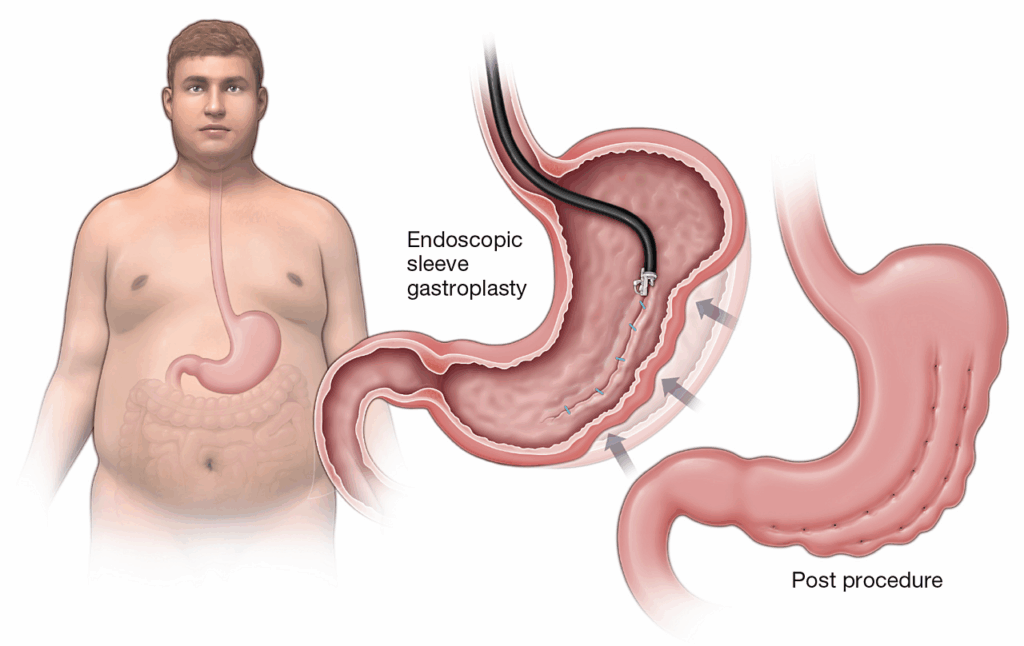

When you choose Laparoscopic Sleeve Gastrectomy with Dr. Abhay Agrawal, the best bariatric surgeon in Mumbai, you're opting for a powerful, minimally invasive procedure designed to reduce your stomach size, leading to significant weight loss. This surgery, performed through tiny incisions, offers faster recovery times and less post-surgical discomfort, making it ideal for those seeking lasting results with minimal downtime. Imagine stepping into a future where obesity no longer holds you back—now is the moment to take control and make that vision a reality with the best bariatric surgeon in Mumbai. Call now to take the first step!